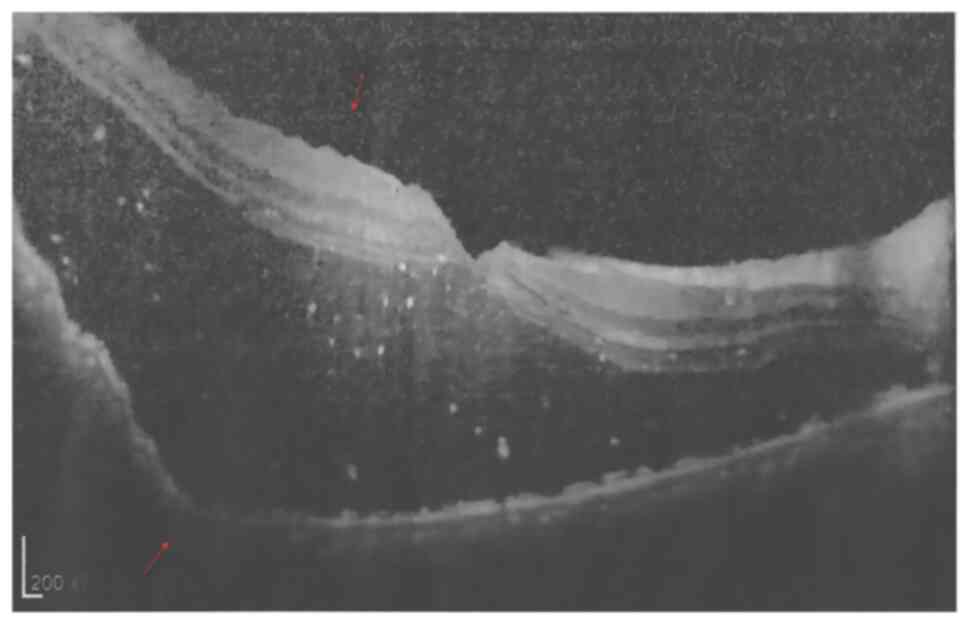

Figure 3

Optical coherence tomography at

initial consultation shows elevation of the retina with associated

inferior retinal detachment (red arrow) (scale bar, 200 µm).